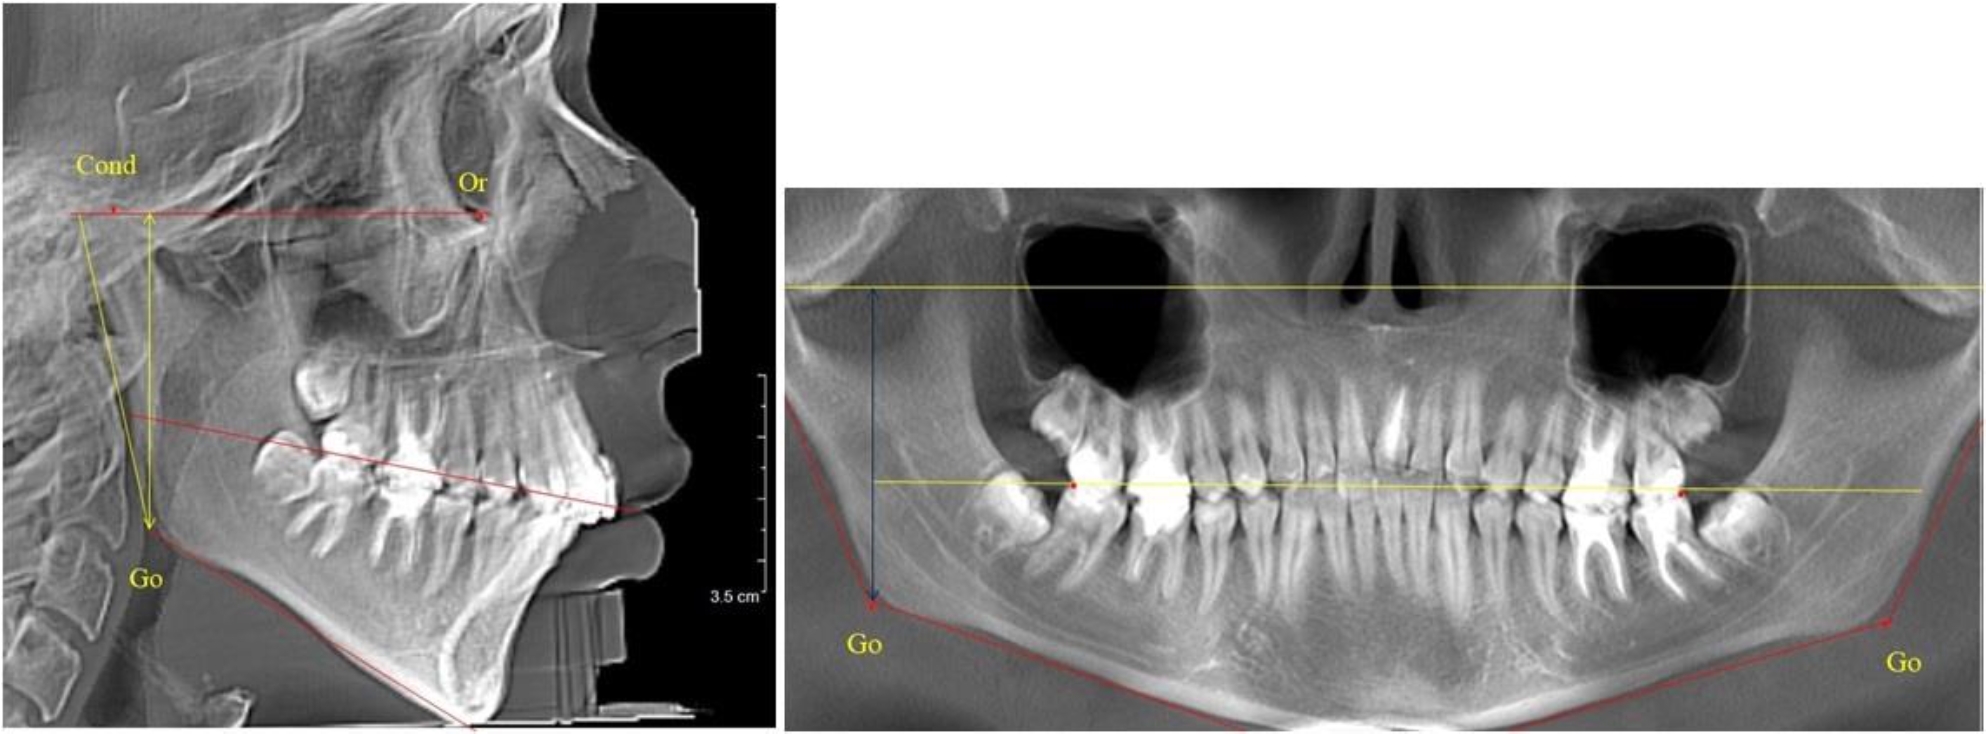

В 4-й группе были проанализированы 12 комплектов рентгенограмм, что составило (11,32 ± 3,08) % от общего числа. На всех рентгенограммах произошла полная смена всех молочных зубов постоянными. Окклюзионная линия делила ветвь на два отдела (рис. 4).

Рис. 4. ТРГ пациента после смены всех молочных резцов

Высота ветви у детей 4-й группы составляла (54,27 ± 2,59) мм, что было достоверно больше, чем у детей 1-й группы (р ˂ 0,05). При этом высота верхней окклюзионно-суставной части была (32,51 ± 1,72) мм, а нижней – (21,76 ± 1,42) мм. Высота верхней части была больше нижней, что и определяло особенности соразмерности частей ветви нижней челюсти в анализируемый возрастной период.

Относительные показатели соразмерности частей ветви нижней челюсти показали, что отношение высоты верхней части ветви к нижней в среднем составляло 1,49 ± 0,12. Отношение общей высоты ветви к верхней ее части составляло 1,67 ± 0,14, а отношение общей высоты ветви к нижней ее части было 2,49 ± 0,15, что и определяло особенности соразмерности частей ветви нижней челюсти в анализируемый возрастной период.

В 5-й группе были проанализированы 14 комплектов рентгенограмм, что составило (13,21 ± 3,29) % от общего числа. На всех рентгенограммах отмечен очередной этап подъема высоты прикуса, обусловленный прорезыванием вторых постоянных моляров. Окклюзионная линия делила ветвь на два отдела (рис. 5).

Рис. 5. ТРГ и ОПТГ пациента после смены молочных зубов и прорезывания вторых постоянных моляров

Высота ветви у детей 5-й группы составляла (62,87 ± 3,62) мм, что было достоверно больше, чем у детей других групп (р ˂ 0,05). При этом высота верхней окклюзионно-суставной части была (40,23 ± 2,01) мм, а нижней – (22,64 ± 1,78) мм. Высота верхней части была вдвое больше нижней, что и определяло особенности соразмерности частей ветви нижней челюсти в анализируемый возрастной период.

Относительные показатели соразмерности частей ветви нижней челюсти показали, что отношение высоты верхней части ветви к нижней в среднем составляло 1,78 ± 0,18. Отношение общей высоты ветви к верхней ее части составляло 1,56 ± 0,12, а отношение общей высоты ветви к нижней ее части было 2,78 ± 0,14, что и определяло особенности соразмерности частей ветви нижней челюсти в анализируемый возрастной период.